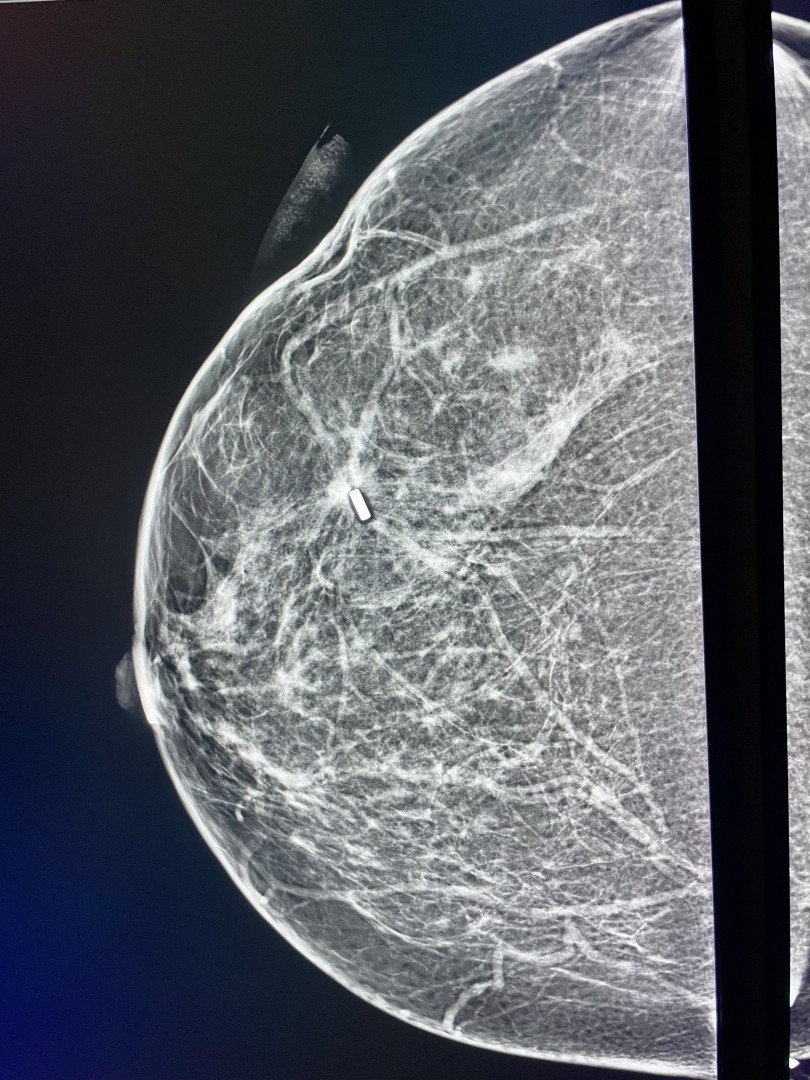

VIDEO: Lékaři v novoměstské nemocnici umí odhalit nádor prsu pomocí magnetického zrna. Jako první v kraji

Lékaři v novoměstské nemocnici umí odhalit nádor prsu pomocí magnetického zrna. Jako první v kraji